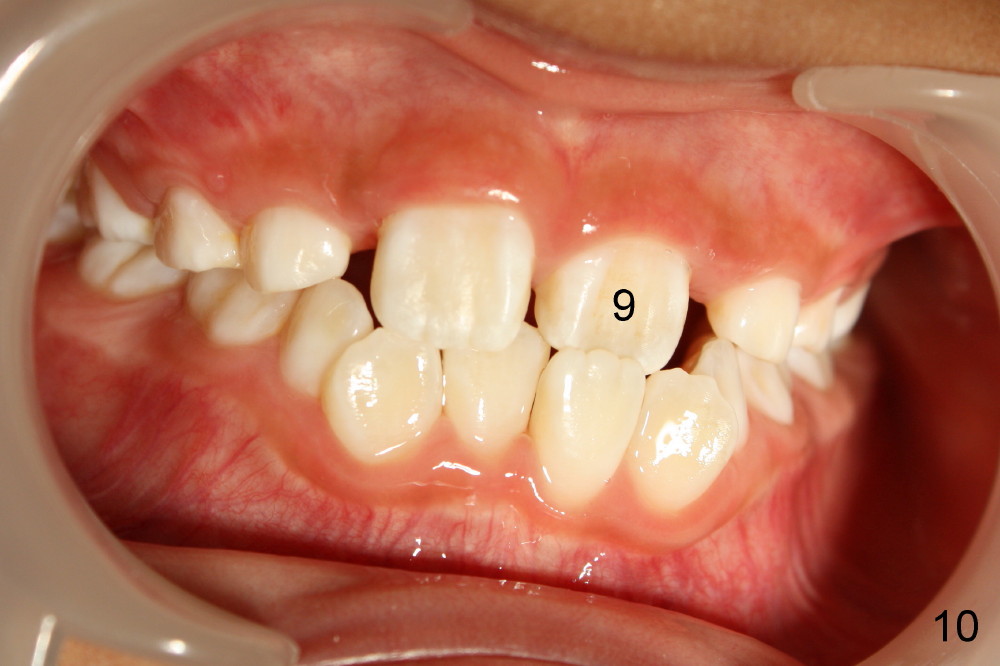

Now Devon is 7.5 years old. There is diastema between the centrals (Fig.9). #9 is in cross bite (Fig.10,11), while the lower incisors are crowded.

现在Devon七岁半,中切牙之间缝隙大(图九至十一:8,9),乳侧切牙已经脱落,但是没有足够间隙让恒侧切牙(图九:7, 10(C, H:乳尖牙))萌出,左上中切牙反合(图十:9),下切牙拥挤。